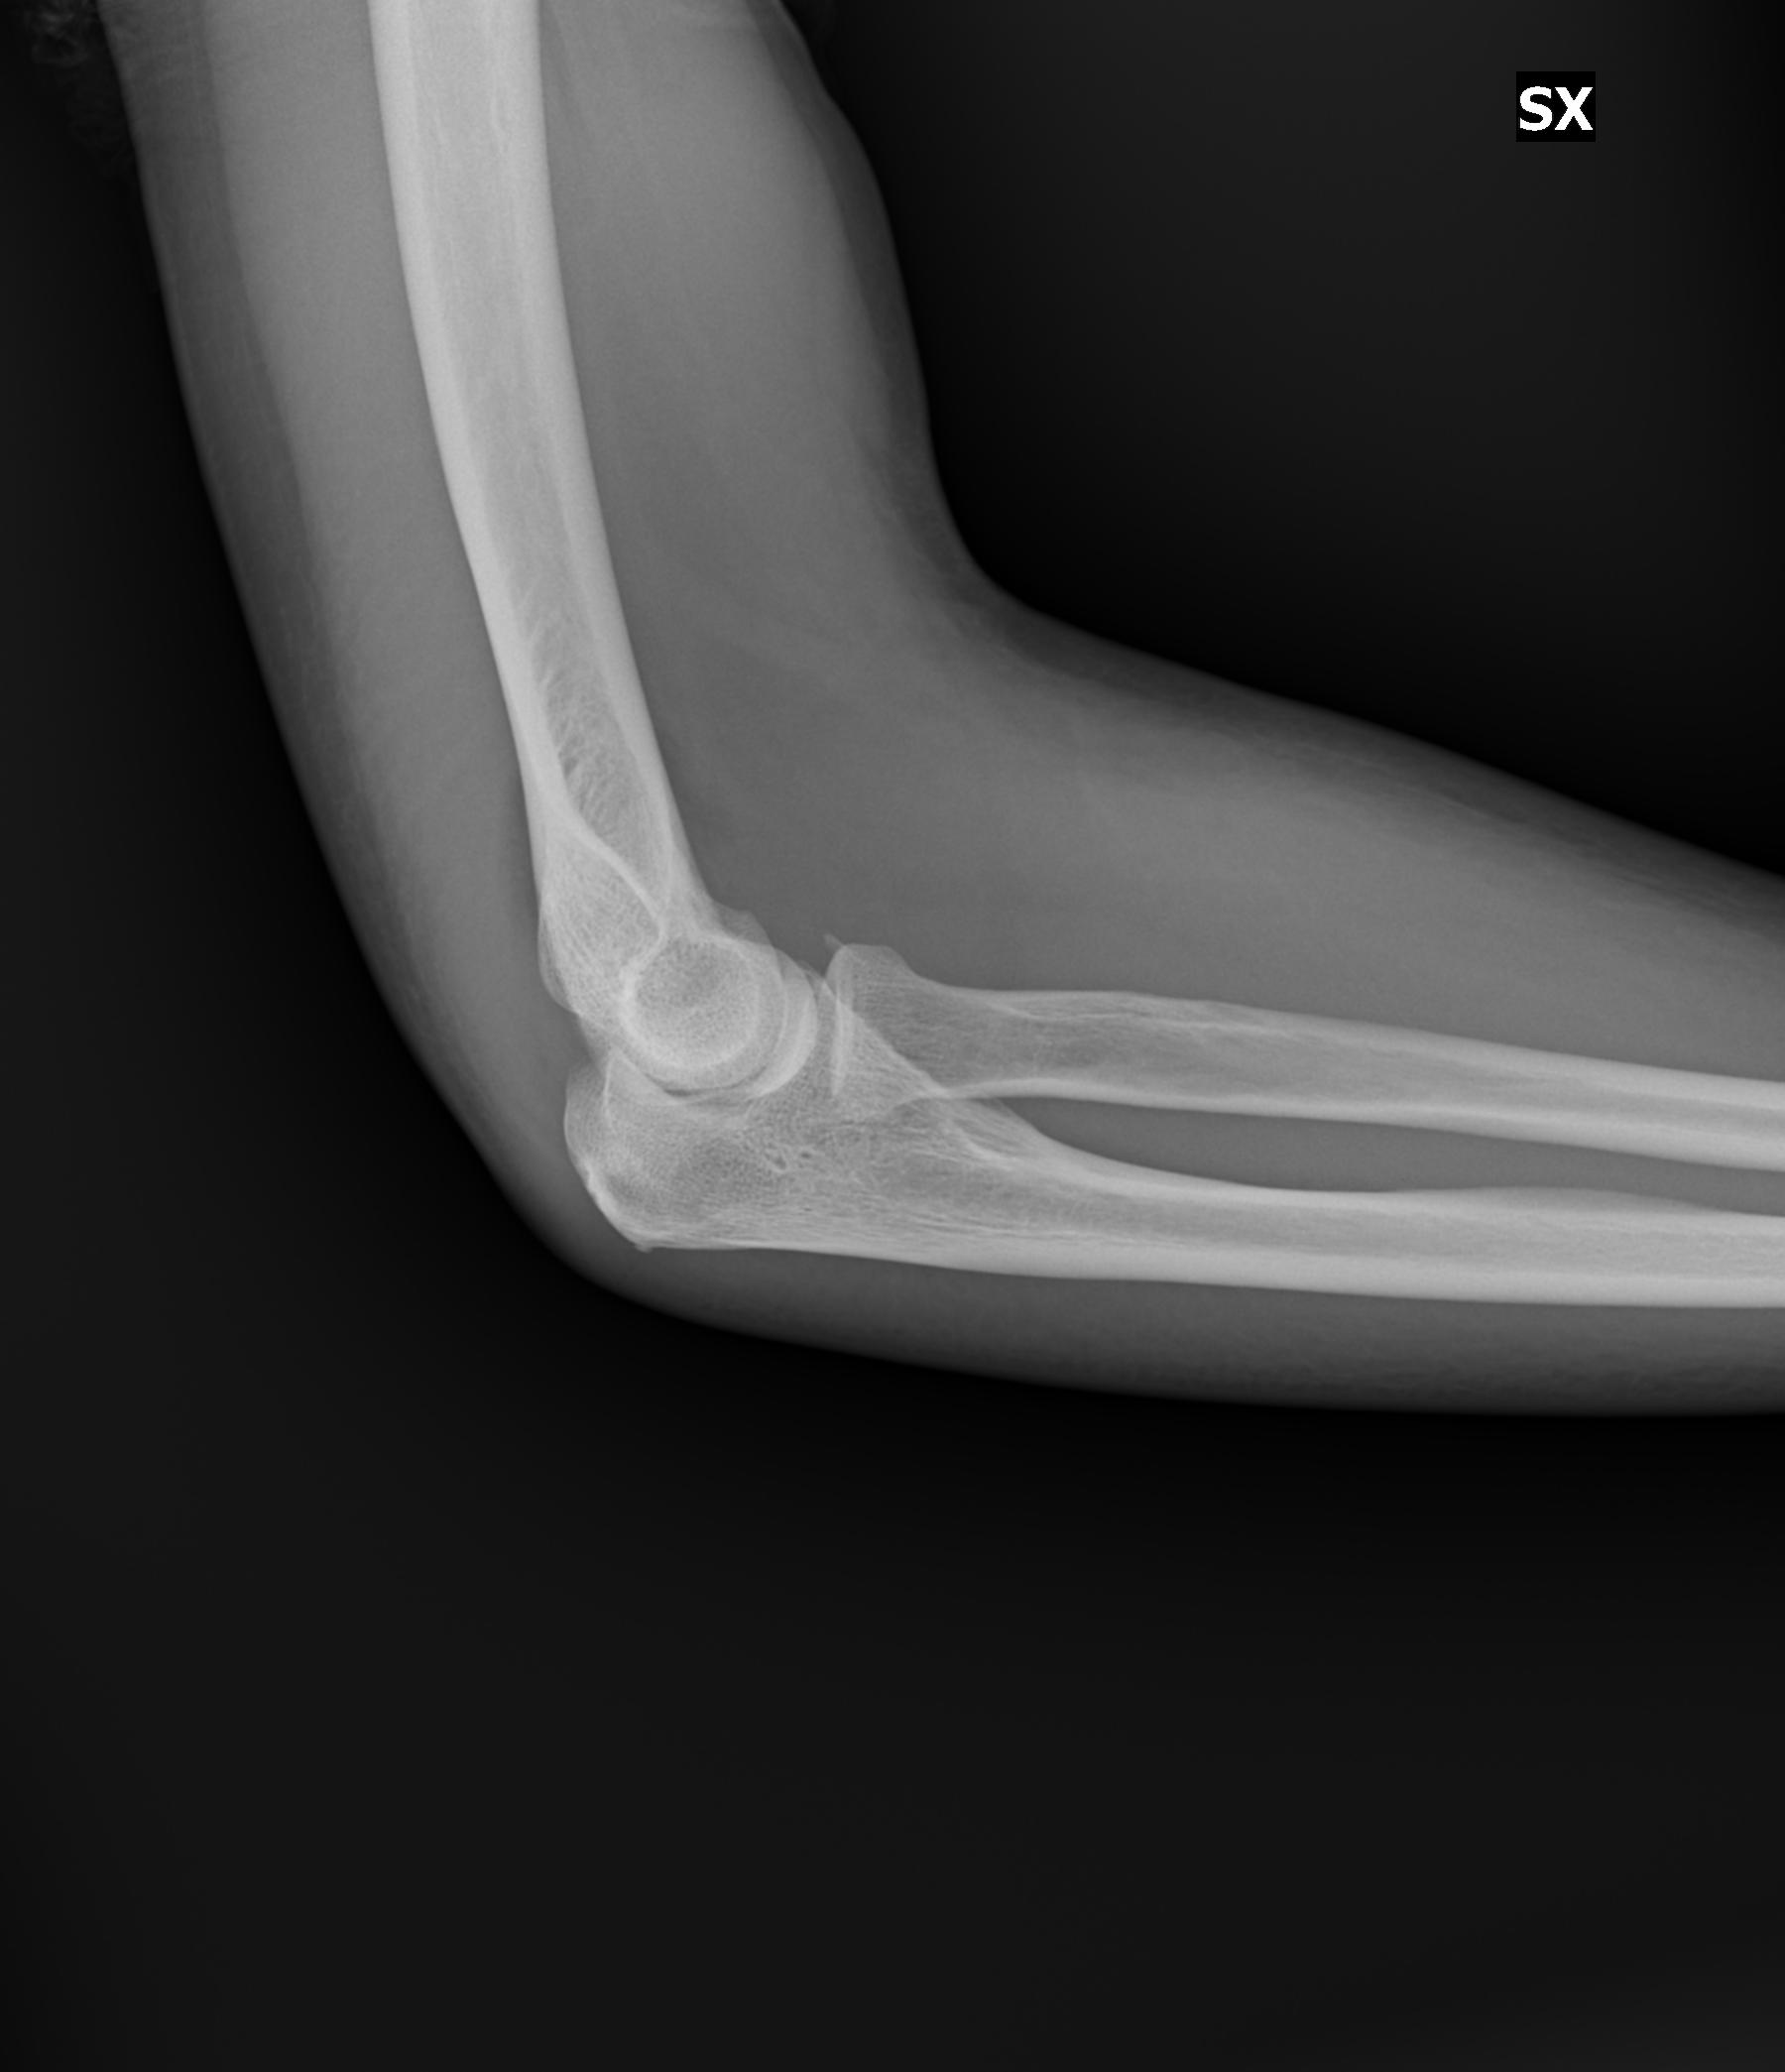

Giorno 16 Gen camminando cado inciampando in un dislivello. Al pronto soccorso fanno Rx al Gomito (due proiezioni), polso e mano Sx . Dopo visita ortopedica la diagnosi risulta: TRAUMA CONTUSIVO ARTO SUP SX.

Giorno 21 rifaccio i Rx altrove e mi risulta invece: DISTACCO LAMELLARE DEL CAPITELLO RADIALE.

1) E’ possibili capire di che entità è la lesione? Mi potrebbero bastare i 17/18 gg di reggibraccio? (invio in jpg i raggi fatti successivamente).

invio in allegato i raggi effettuati

IMG00002.jpg

[ 101.89 KiB | Osservato 976 volte ]

IMG00001.jpg

[ 147.99 KiB | Osservato 976 volte ]